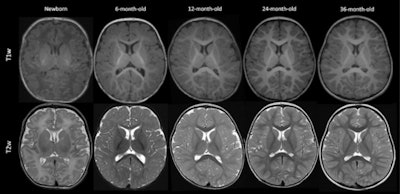

Myelin is a sheath that forms around nerves, including those in the brain and spinal cord, the team explained. Its maturation begins before birth and continues until a child is about three. Pediatric radiologists assess myelin maturation by tracking age-appropriate milestones and comparing brain MRI images to normal "templates." However, this task is tricky and requires years of expertise, the authors noted. That's why deep learning could help.